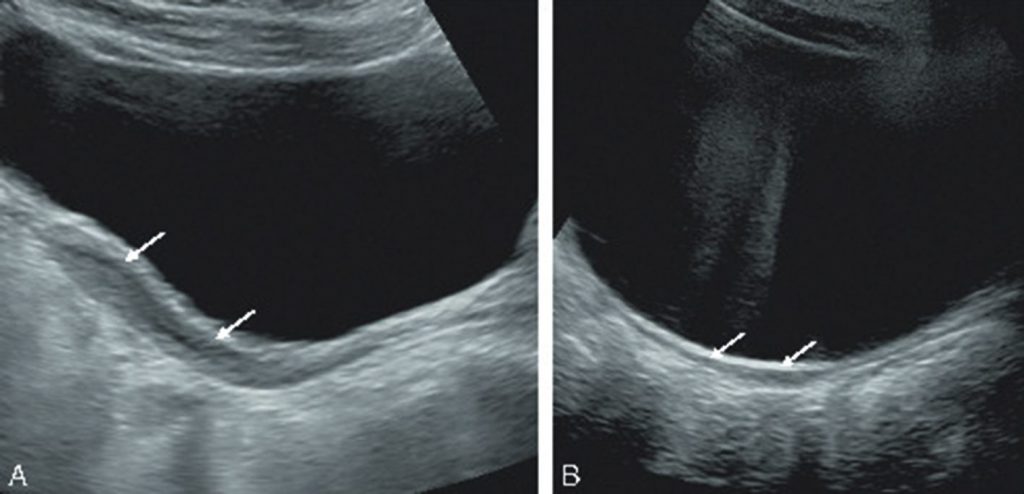

À l’échographie, il existe un vagin et un utérus impubères en l’absence de traitement (figure 109.1). Les ovaires peuvent être présents mais régressent très précocement. Ils peuvent ne pas être visualisés lors de l’examen.

Fig. 109.1. Échographies du pelvis en coupe longitudinale chez deux jeunes filles de 13 ans.

Aspect normal d’un utérus (A, flèches) à cet âge. L’échographie (B) montre, en arrière de la vessie, un utérus impubère (flèches) de petite taille chez une patiente présentant un syndrome de Turner.

Source : CERF, CNEBMN, 2022.